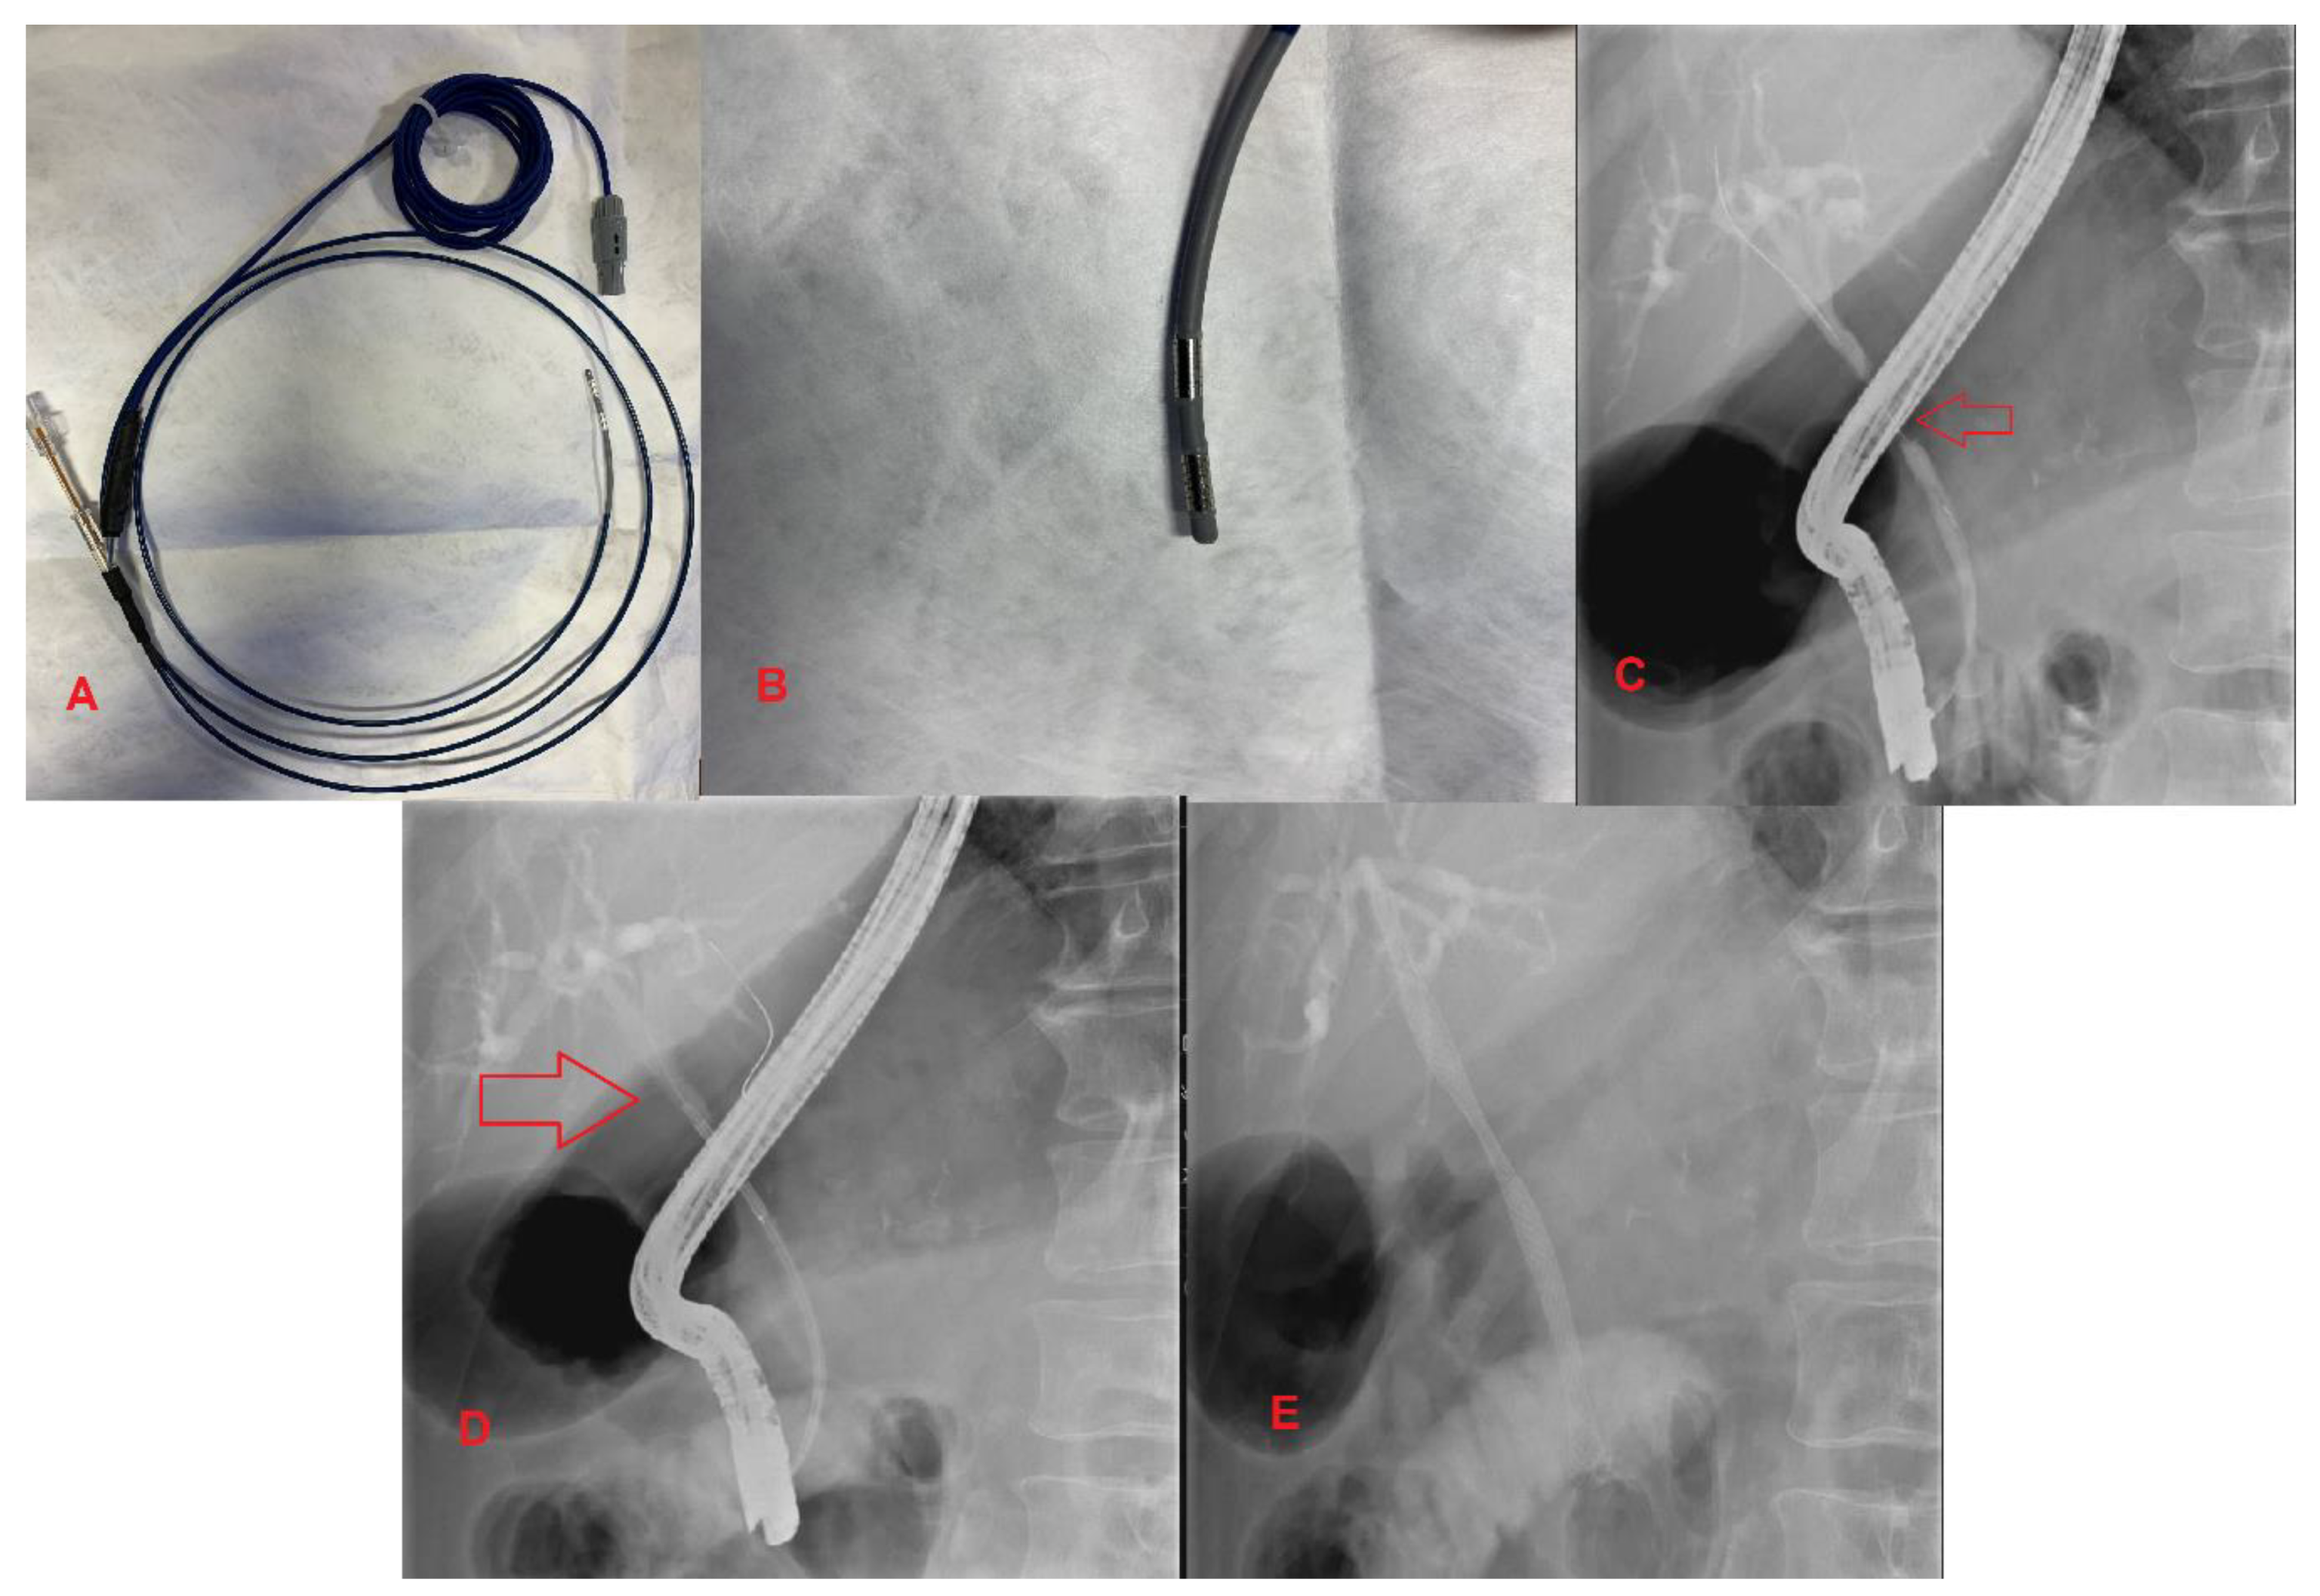

Prior to the development of RFA, endoscopic directed treatment of unresectable MBS consisted of photodynamic therapy (PDT). This procedure involves injection of a photosensitizing chemical with subsequent laser application to the lesion, leading to tissue necrosis. PDT showed promising results; however, there was a significant increase in complications resulting in low utilization [26]. RFA is a novel alternative to PDT in the palliative approach to unresectable MBS. It involves administering thermal energy to strictures, leading to necrosis and cell death. The two RFA catheters in use are the Habib EndoHPB Bipolar Radiofrequency Catheter by Boston Scientific and the ELRA (Endoluminal Radiofrequency Ablation) by Taewoong Medical in South Korea [27]. These RFA catheters can be advanced over a guidewire towards the target lesion during ERCP (Figure 3).

Figure 3.

Extrahepatic Cholangiocarcinoma. (A,B) Habib Endo HPB Bipolar Radiofrequency Catheter; (C) Malignant common bile duct stricture; (D) The red arrow indicates a radiofrequency ablation catheter in place across a stricture; (E) UCSEMS placement status post RFA therapy.

One challenging aspect of RFA is limiting ablation to healthy tissue surrounding the malignancy. A novel balloon catheter-based RFA system has been designed to solve this problem. Inoue et al. performed an experimental study using the balloon catheter-based RFA system and found that the accuracy of ablation was significantly improved, with a reduction in normal cell ablation [30]. In conclusion, RFA therapy significantly prolongs survival and improves stent patency for pancreatic cancer and cholangiocarcinoma. However, RCTs are needed to quantify the absolute survival benefit and determine the role of RFA in patients with unresectable HPB malignancy (Figure 3).